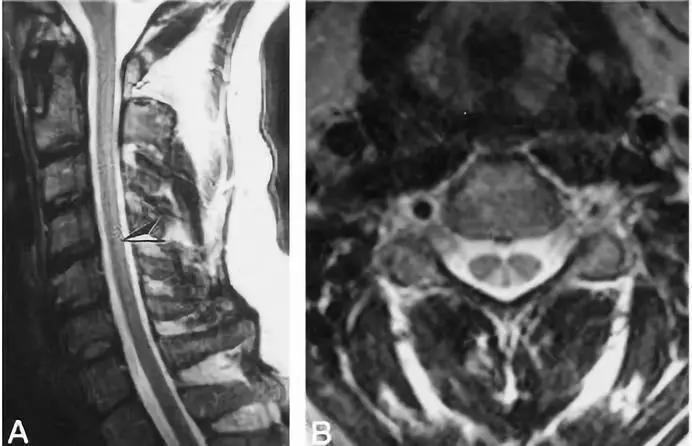

病灶分布于脊髓后索,T2WI高信号,呈倒“V”字征,明显强化

病灶分布于脊髓后索,T2WI高信号,呈倒“V”字征,铜补充治疗后病灶消失

病灶分布于脊髓后索,T2WI高信号,呈倒“V”字征